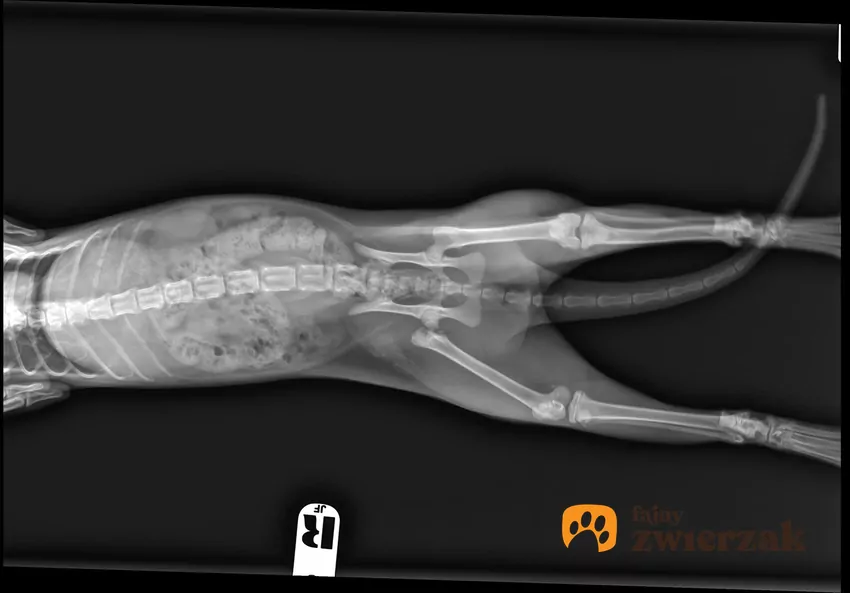

Łokieć u kota istnieje i znajduje się dokładnie tam, gdzie u większości ssaków – w połowie długości kończyny przedniej. Staw łokciowy łączy kość ramienną z kością łokciową i promieniową. Dzięki nim zwierzę może zginać i prostować łapę, a także stabilnie podpierać ciało podczas chodzenia lub lądowania po skoku.

Jeśli delikatnie pomacasz przednią kończynę pupila od barku w dół, wyczujesz najpierw dość szeroki staw barkowy, potem długą kość ramienną, a następnie wyraźne zgięcie – to właśnie łokieć. Leży on znacznie bliżej tułowia niż ludzki łokieć i jest ukryty pod gęstą sierścią oraz warstwą mięśni, dlatego na co dzień go nie widać. Gdy kot siedzi, łokcie stają się wyraźniejsze – wyglądają wtedy jak małe wyrostki po bokach klatki piersiowej.

Koty mają również kolana, ale ich położenie i orientacja mylą wielu ludzi. Nasz staw kolanowy zgina się do tyłu, a mruczka – do przodu. Dlatego możemy usłyszeć stwierdzenie, że koty nie mają kolan, tylko same stawy skokowe. To mit.

Staw kolanowy czworonoga znajduje się mniej więcej w 1/3 długości tylnej kończyny, licząc od biodra w dół. Poniżej kolana jest bardzo długa kość piszczelowa i strzałkowa, a potem potężny staw skokowy, który opiekunowie najczęściej mylą z kolanem, ponieważ znajduje się wysoko nad ziemią i zgina się w tę samą stronę co nasze kolano.